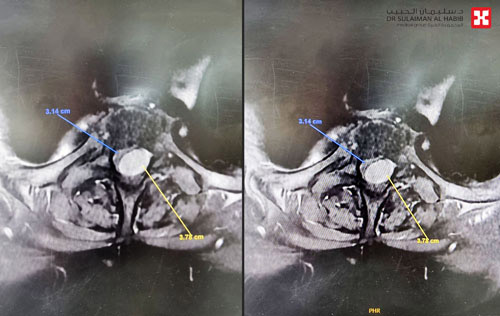

وأوضح د. النبهان أن كلتا الإصابتين تثيران الأعراض التي تشكو منها المريضة، لذلك تم إعادة فحصها بالرنين المغناطيسي للتأكد من حجم الورم ومدى الضغط الذي يشكله على النخاع الشوكي، وتم التأكد بأن الورم هو المسبب الأساسي لمتاعب السيدة.